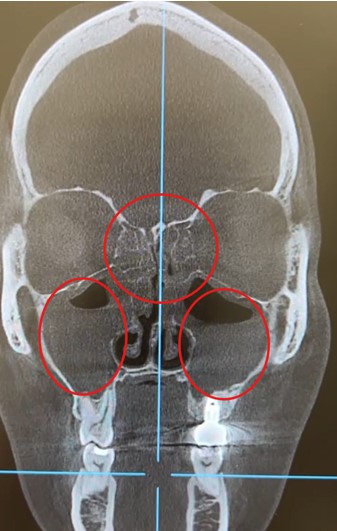

Результаты КТ (от августа 2025):

- Тотальное затемнение в решетчатой пазухе (этмоидальный синусит).

- Тотальное затемнение в обеих верхнечелюстных (гайморовых) пазухах (двусторонний гайморит).

- Затемнение в лобных пазухах, более выраженное слева (фронтит).

КТ-снимок (коронарная проекция): красными кружкам указаны области тотального снижения пневматизации в верхнечелюстных и решетчатой пазухах, характерные для пансинусита.